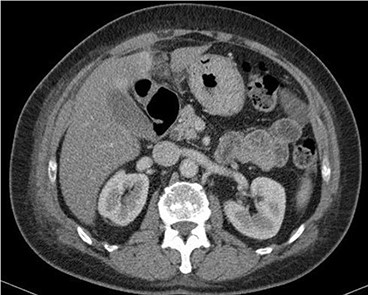

A 53-year-old fit and well woman presented to the emergency department with acute epigastric and right hypochondrium pain with a positive Murphy’s sign of the abdomen. The patient was anicteric and apyrexial. Blood tests performed revealed a white cell count of 13.6 × 109/L and a C-reactive protein of 110 U/L. Liver function tests, amylase and urea and electrolytes were unremarkable. A working diagnosis of acute cholecystitis was made and the patient commenced on intravenous fluids and intravenous antibiotics. Abdominal ultrasound was performed, which demonstrated no gallstones nor choledocholithiasis and was essentially normal. Given the raised inflammatory markers and persistent abdominal pain, CT scan was performed (Fig. 1). This revealed a 32 × 22-mm oval-shaped fat density lesion with peripheral hyper attenuation adjacent to the falciform ligament, representing intraperitoneal focal fat infarction of the fatty appendage of falciform ligament. Sagittal reconstruction showed a central hyperdense thrombosed vessel secondary to torsion of the falciform ligament (Fig. 2).

Contrast-enhanced CT scan shows a 32 × 22-mm oval-shaped fat density lesion with peripheral hyperattenuation and central hyperdense dot adjacent to falciform ligament. There is surrounding oedema and inflammation. Gall bladder is noted to be unremarkable. Features represent intraperitoneal focal fat infarction of fatty appendage of falciform ligament.